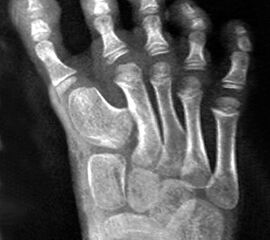

Angeborene Deformität und Fehlanlage 1. Strahl (eigenes Bildmaterial) (Vispo-Seara 1998, Hefti 1998)

Abbildung 9

Mit zunehmendem Wachstum und Alter wird die Abweichung der Großzehe zunehmend symptomatisch. Es können keine normalen Schuhe getragen werden, es entstehen kosmetisch schwerwiegende Probleme. Deshalb wird zu einer frühzeitigen Korrektur im Säuglings- und Kleinkindalter geraten 12, d. h. im 9. – 24 Lebensmonat 215.

Die Therapie ist immer operativ, wobei sich der individuelle Eingriff an der jeweiligen Dysplasie orientiert.

Gute Erfolge zeigen die Entfernung akzessorischer Knochen (Mc Elvenny, 1941; Corte-Real, 1998), sowie eine iatrogene Syndaktylie zwischen der 1. und 2. Zehe.

Möglich sind weiterhin subkapitale Osteotomien des Metatarsale I sowie eine auf- klappende Osteotomie am Os cuneiforme mediale (Hefti, 1998) mit K-Draht-Fixation oder die 1958 von Farmer 5 beschriebene Technik mit ausgeführter Lappentechnik (de Valentine, 1992).